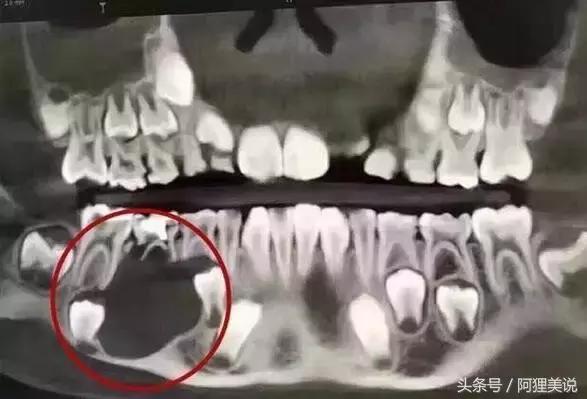

5龄童20颗乳牙全部蛀光

嘴里20颗乳牙,全部龋坏。

一开始,田田患的是“奶瓶龋”,

这种蛀牙往往是因为长期使用奶瓶造成的,

因为牛奶、母奶、果汁及糖水等,

都含有不同成分可发酵醣类,

经变形链球菌利用之后而产生酸,

长时间停留在牙齿周围,

造成牙齿表面脱钙。

儿童六龄齿最容易龋坏

一旦长出,终身不再替换

据了解,

在儿童龋齿中,

发病率最高的是窝沟龋,

约占儿童龋齿的80%,

而“六龄齿”(即第一恒磨牙)就是窝沟龋的好发部位。